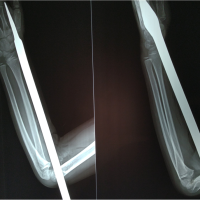

A 22-year-old male patient presented in our outpatient department with pain in the right sternoclavicular region which aggravated on overhead activities. He sustained a fall on the right outstretched hand during a bike accident 8 h before presenting to us. On clinical examination, there was tenderness over the medial sternoclavicular joint as well as posterior dip in the medial clavicle (Fig. 1). This led us to clinically suspect a posterior sternoclavicular dislocation. The radiographs appeared normal (Fig. 2) so we advised a 3D reconstruction CT imaging of the right clavicle and sternum. CT images were suggestive of a posterior dislocation of the medial end of the clavicle (Fig. 3). However, one section of the CT appeared to show a flake of bone attached to the sternum. Medial clavicular physeal injury was a secondary diagnosis which was kept in consideration. We decided to take the patient up for closed reduction under anesthesia and covert to open reduction if closed attempts failed.